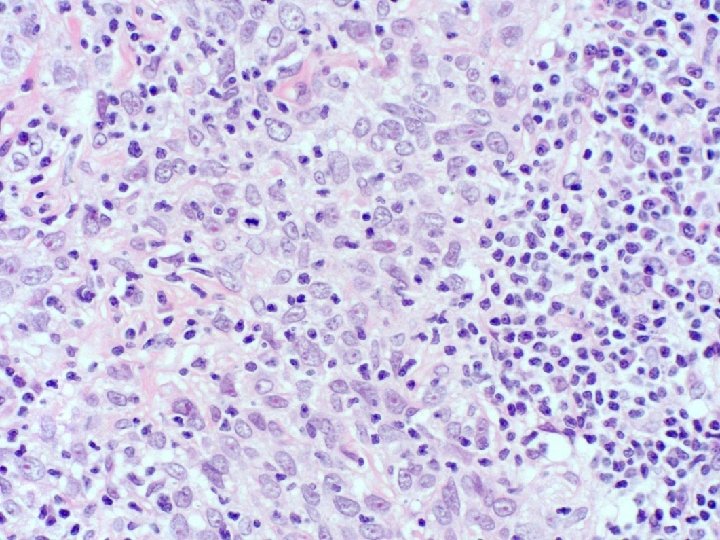

�Case number: 189 �Female aged 48 years. �A. L. L. Had bone marrow transplant.

�Case number: 189 �Female aged 48 years. �A. L. L. Had bone marrow transplant. �Had susequent Gv. HD. �Now thickened red, swollen skin �? Leukaemic infiltrate. �Positive for CD 79 a, CD 20, CD 10, CD 34, Td. T. �Negative for CD 2, CD 3 and CD 117.

� Most popular diagnosis � B lymphoblastic lymphoma